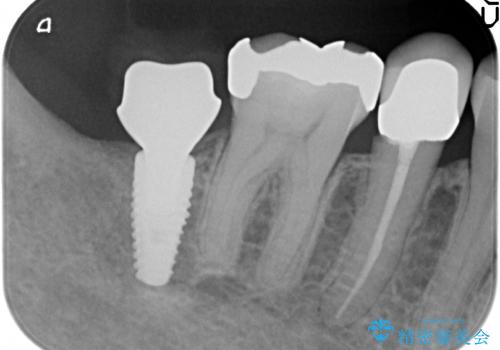

- 右下7番にインプラント治療を行った症例です。

CT撮影を行い状態を確認後、インプラント(ストローマン)の埋入(一次手術)を行いました。

インプラントと骨の定着を待った後に二次手術を行い、カスタムアバットメント、オールセラミッククラウンによる補綴を行いました。